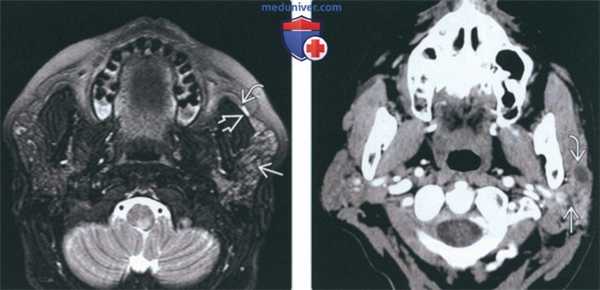

(Слева) КТ с КУ, аксиальная проекция. Подросток с обструктивным паротитом, определяется характерное увеличение правой околоушной железы с накоплением в ней контрастного вещества и расширение протока железы. В дистальном отделе протока обнаружен конкремент.

(Справа) КТ без КУ, аксиальная проекция. Диффузное увеличение правой околоушной железы, возникшее у пациента после травмы. Также имеется отек окружающей жировой клетчатки.

2. КТ при остром паротите:

• КТ без контрастирования

о Бактериальный: увеличенная железа повышенной плотности с нечеткими контурами

о Вирусный: увеличенная железа повышенной плотности

о Обструктивный: обычно удается визуализировать камень в протоке железы

о Аутоиммунный: окружающая жировая клетчатка поражается в меньшей степени

• КТ с КУ:

о Бактериальный: увеличенная железа, равномерно накапливающая контрастное вещество:

- Воспалительная исчерченность жировой клетчатки

- При наличии абсцесса - содержимое пониженной плотности с кольцом накопления контраста

о Вирусный: увеличенная околоушная железа, незначительно накапливающая контрастное вещество о Обструктивный: проток железы увеличен, стенки накапливают контраст, в остальном картина аналогична бактериальному воспалению

о Аутоиммунный: исчерченность жировой клетчатки меньше:

- При длительном процессе возможно расширение протока